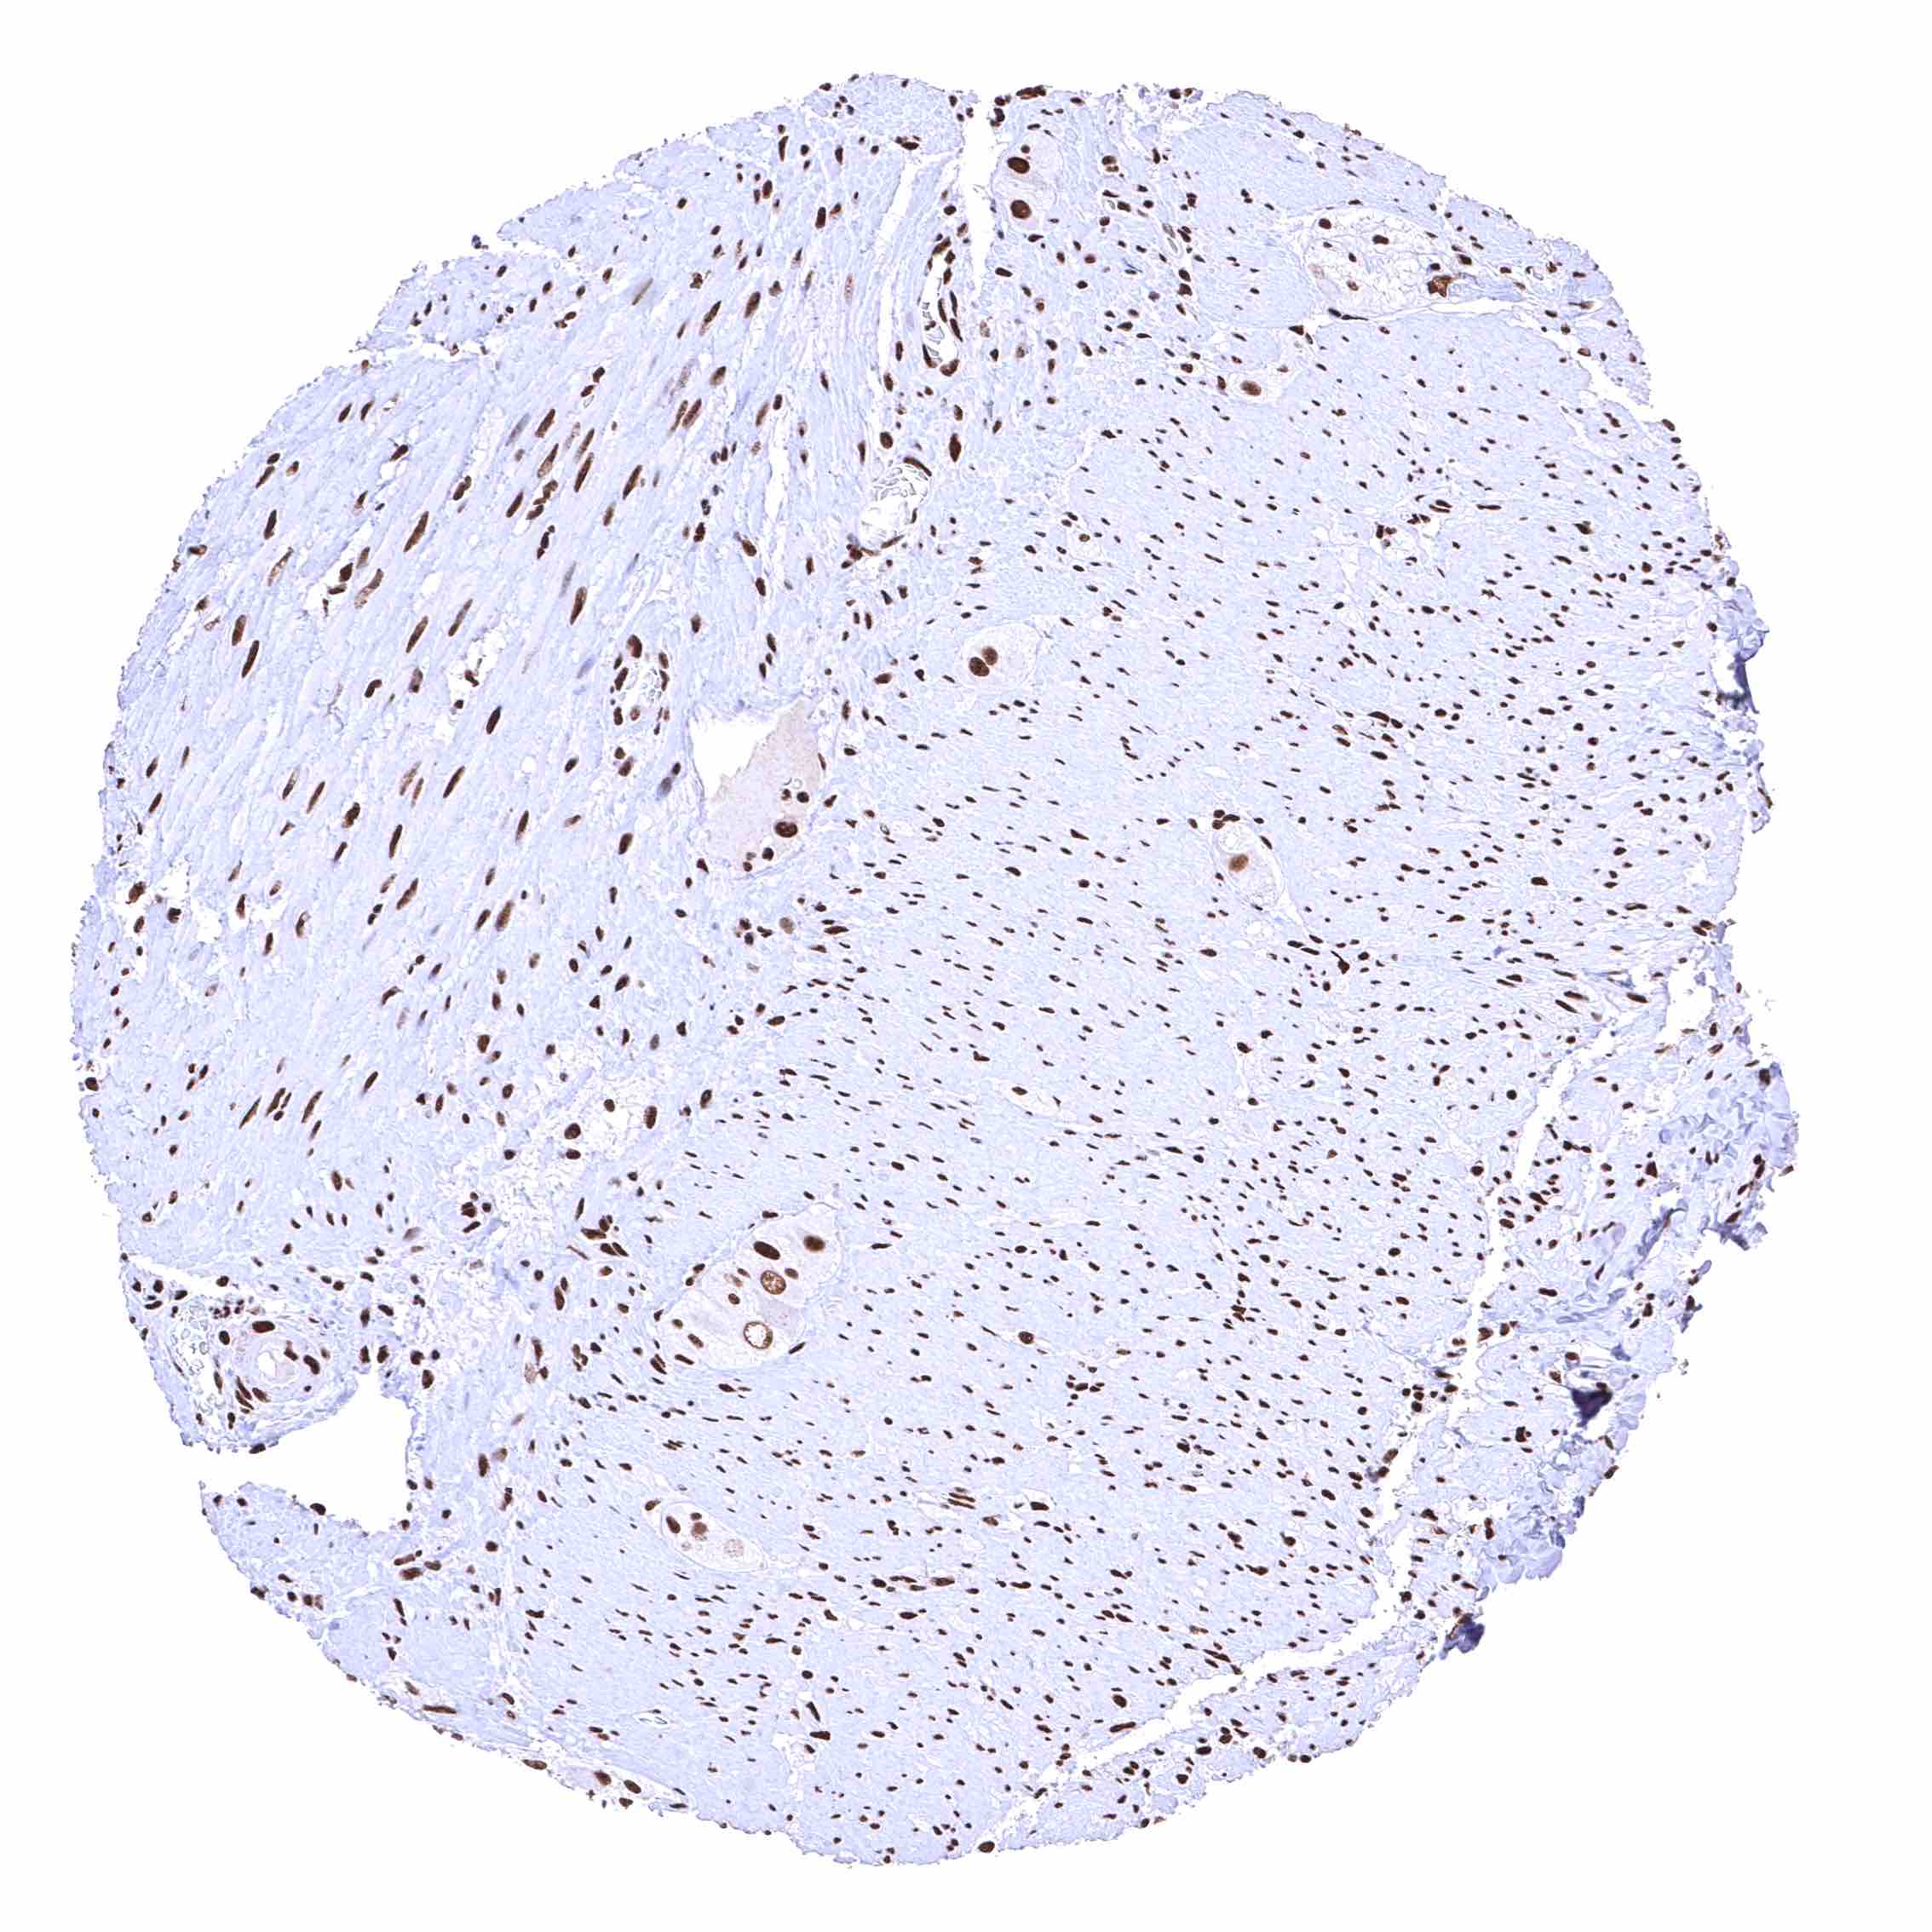

Heart muscle – Distinct nuclear BRD4 staining of all cells. The additional cytoplasmic staining of some muscle cells may represent an antibody specific cross-reactivity.